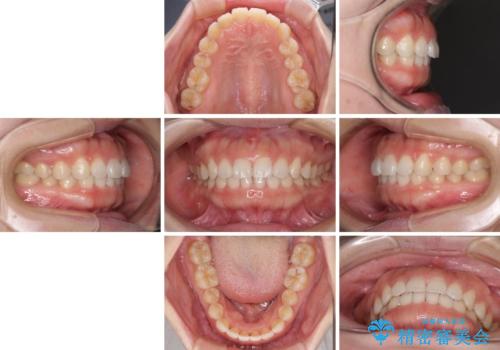

1日22時間の装着時間をしっかり守ってくださったので、1年程度で治療を終えることができました。

1セットのマウスピースで概ね治療を終えたのですが、前歯僅かな叢生が残ったため、2セット目のマウスピースで仕上げました。

気にしていた口元の印象が改善され、患者様には大変満足していただきました。